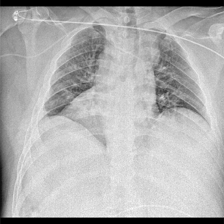

| Raw image | GT | Swin UNETR | nnU-Net | LViT | GuideDecode | MMI-UNet | Ours |

As shown in Table I, our SSA framework achieves state-of-the-art (SOTA) performance on both datasets. On QaTa-COV19, SSA achieves a Dice score of 91.65%, significantly outperforming the previous SOTA method (MLMoE, 91.19%). This demonstrates the effectiveness of our DSOT and CDG. The superior performance on MosMedData+ further validates the generalization capability of our approach. The qualitative results in Fig. 3 demonstrate that our model accurately segments infected areas while suppressing irrelevant regions.